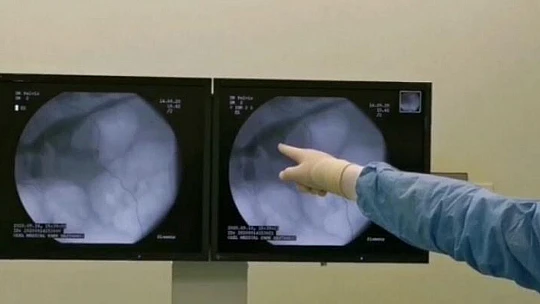

3 çocuk 1 torun sahibi 54 yaşındaki Fuat Salar, 1988 yılında trafik kazası sonrası geçirdiği rahatsızlık ve ameliyatın ardından sol böbreğini kaybetti. Bir yıl sonrasında ise sağ böbreğinden açık taş ameliyatı olan Salar, en son bir ay önce idrar yapamama şikayeti ile Medical Park Elazığ Hastanesi’ne başvurdu. Burada Üroloji Uzmanı Op. Dr. Serhat Yentür’ün tedavisine başladığı Salar, yapılan tetkikler sonucunda böbreğinde 3 santimetrelik lezyon ve tümöral hücreler saptandı. Bunun üzerine zor ve riskli olan ‘Perkütan’ yöntemi ile operasyon planlandı. Operasyonda Salar’ın böbreğine yandan girilip orada bir tüp oluşturulduktan sonra böbreğin içine girildi. Ardından hastadaki tümör tur aletleriyle kazındı. Başarılı geçen ameliyatın ardından Salar, 3 gün sonra taburcu edilirken, perkütan yöntemi ile dünya literatüründe 84’üncü vaka olarak kayıtlara geçtiği öğrenildi.

Yapılan tetkikler sonucunda hastanın nadir uygulanan yöntemle sağlığına kavuştuğunu ifade eden Op. Dr. Serhat Yentür, "Hastamıza kontrastsız emar (MR) çektik. MR’de sol böbreğin ana çıkış alanında 3 santimetrelik bir lezyon görüldü. Yani böbrek içinde bir tümör vardı ve onun temizlenmesi lazımdı. Normal şartlarda iki böbreği sağlıklı olan insanda bu böbreği alırız. Ama bu hastamız, tek böbrekli olduğu için böbreği aldığımız zaman hasta direkt diyalize bağlı kalacaktı. Hastamıza bir şans tanıdık ve dünyada çok nadir yapılan bir yöntemi uygulamaya karar verdik. Bu yöntem böbreğe yandan girilerek orada bir tüp oluşturup böbreğin içine perkütan yöntemi ile girilmesinin ardından tümörü tur aletleriyle kazıma işlemiydi. Bu yöntem ve teknikle ameliyat yaptık ve çok başarılı oldu. Hastamız da takiplerine geldi ve gayet iyi. Kreatinlerinde de artma olmadı. Böbreği koruyarak bu ameliyatı başarılı bir şekilde yapmış olduk. Şimdiye kadar dünyada 83 tane bununla ilgili bildirilmiş vaka var, bizim hastamız 84’üncü oldu. Bunu Elazığ’da Medical Park Hastanesi’nde yaptık ve hastamız gayet iyi durumda. Ameliyattan 3 gün sonra hastamızı ayakta taburcu ederek evine gönderdik. Ameliyattan sonra tekrar orada tümör çıkmaması için böbrekten girdiğimiz alandan ilaç uygulaması yaptık. Her şey istediğimiz gibi gitti. Hastamızın tetkikleri temiz, bundan sonra da kontrollerine devam edeceğiz” diye konuştu.